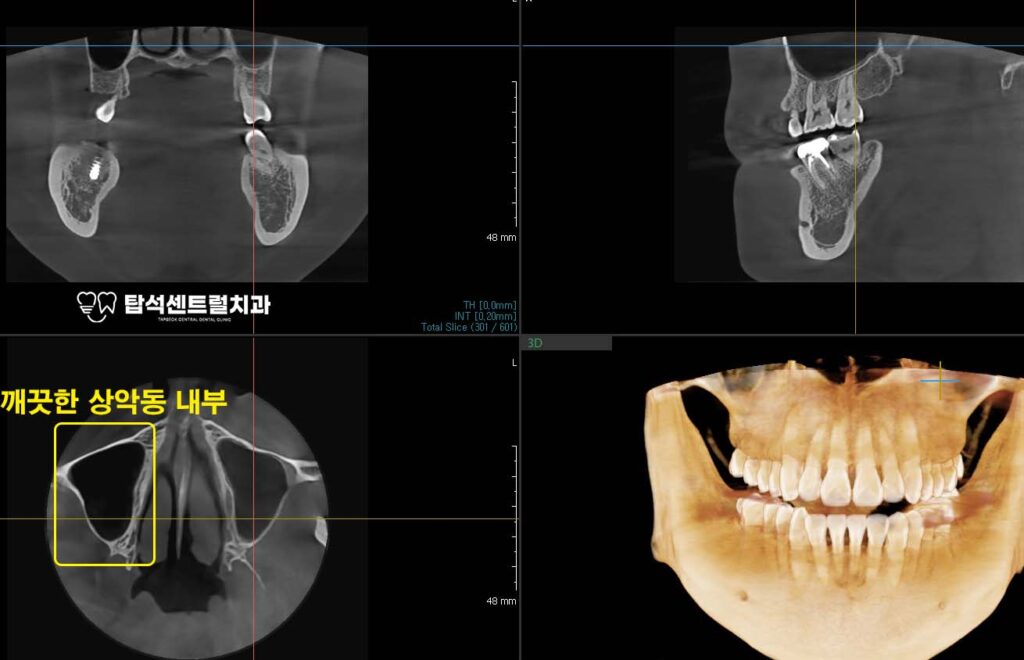

CT 영상에서 한쪽 상악동 내부가

뿌옇게 차 있는 모습이 관찰된다면

그 안에 염증성 물질이 축적되어 있다는

의미로 해석할 수 있습니다.

반대쪽 깨끗하게 비어 있는 모습과 비교하면,

그 차이를 눈으로 비교할 수 있습니다.